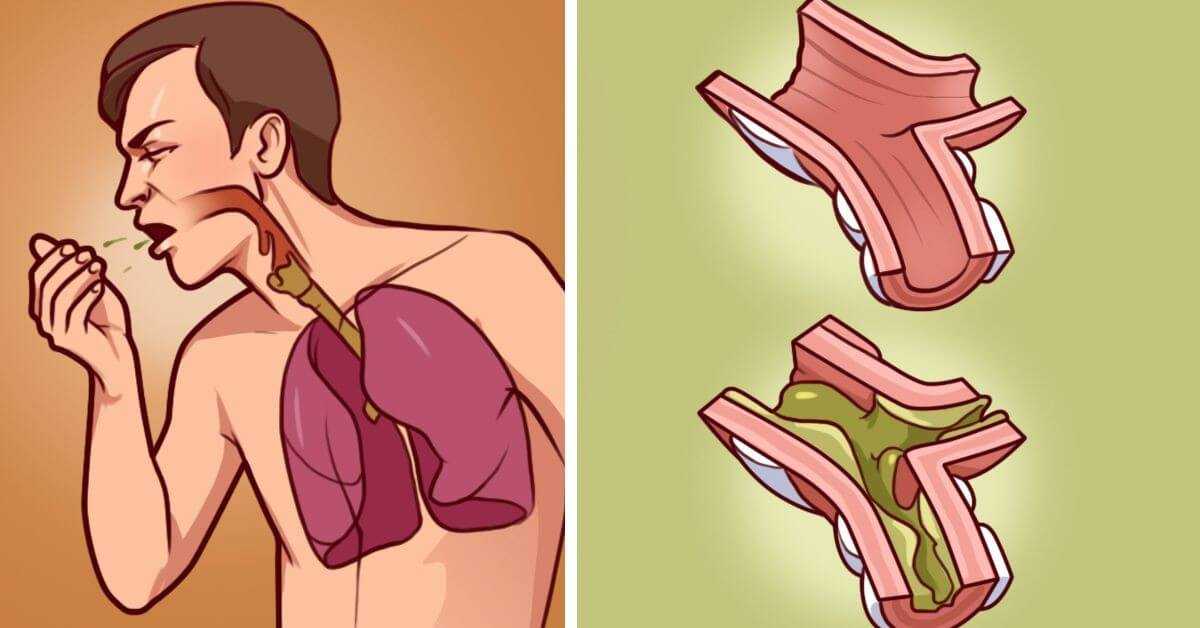

Отхаркивающие средства для взрослых отличаются при сухом и мокром кашле, при прозрачном или гнойном содержимом.

Но это не означает, что можно принимать лекарственные средства по самоназначению, совету случайного знакомого, провизора в аптеке. Особенно опасным это может быть при неуточненном диагнозе, значительном количестве продуцируемого, гнойном или серозном.